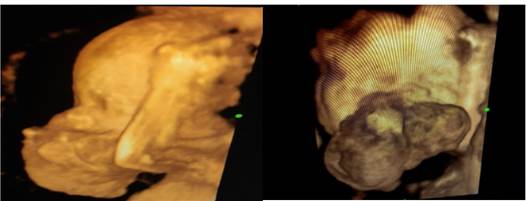

Se le realizó ecografía tridimensional (Figura 3 y 4) y se indicó realizar resonancia magnética nuclear prenatal que respaldara el diagnóstico inicial y para evaluar la extensión; se planteó el caso a cirugía pediátrica para planificación de la resolución posnatal. Se realizó un procedimiento diagnóstico prenatal invasivo, obteniendo como resultado cariotipo normal (46, XX). A las 26 semanas y 4 días se le realizó ecocardiografía fetal encontrándose corazón anatómico y funcional normal y perfil hemodinámico materno fetal adecuado a edad gestacional; además, se evidenció polihidramnios. En el siguiente control ecográfico se evidenció un crecimiento progresivo del tumor hasta 82 x 61 mm, con un polihidramnios estable, y sin evidenciar otro signo de compromiso fetal. Se planificó conducta expectante hasta el término y el manejo periparto pertinente.

Figuras 3 y 4 : Imagen de perfil fetal en reconstrucción volumétrica, donde se evidencia, tumoración en macizo facial, de bordes irregulares, bilobulada, en el 1/3 medio de la cara, que distorsiona la anatomía de la cara.